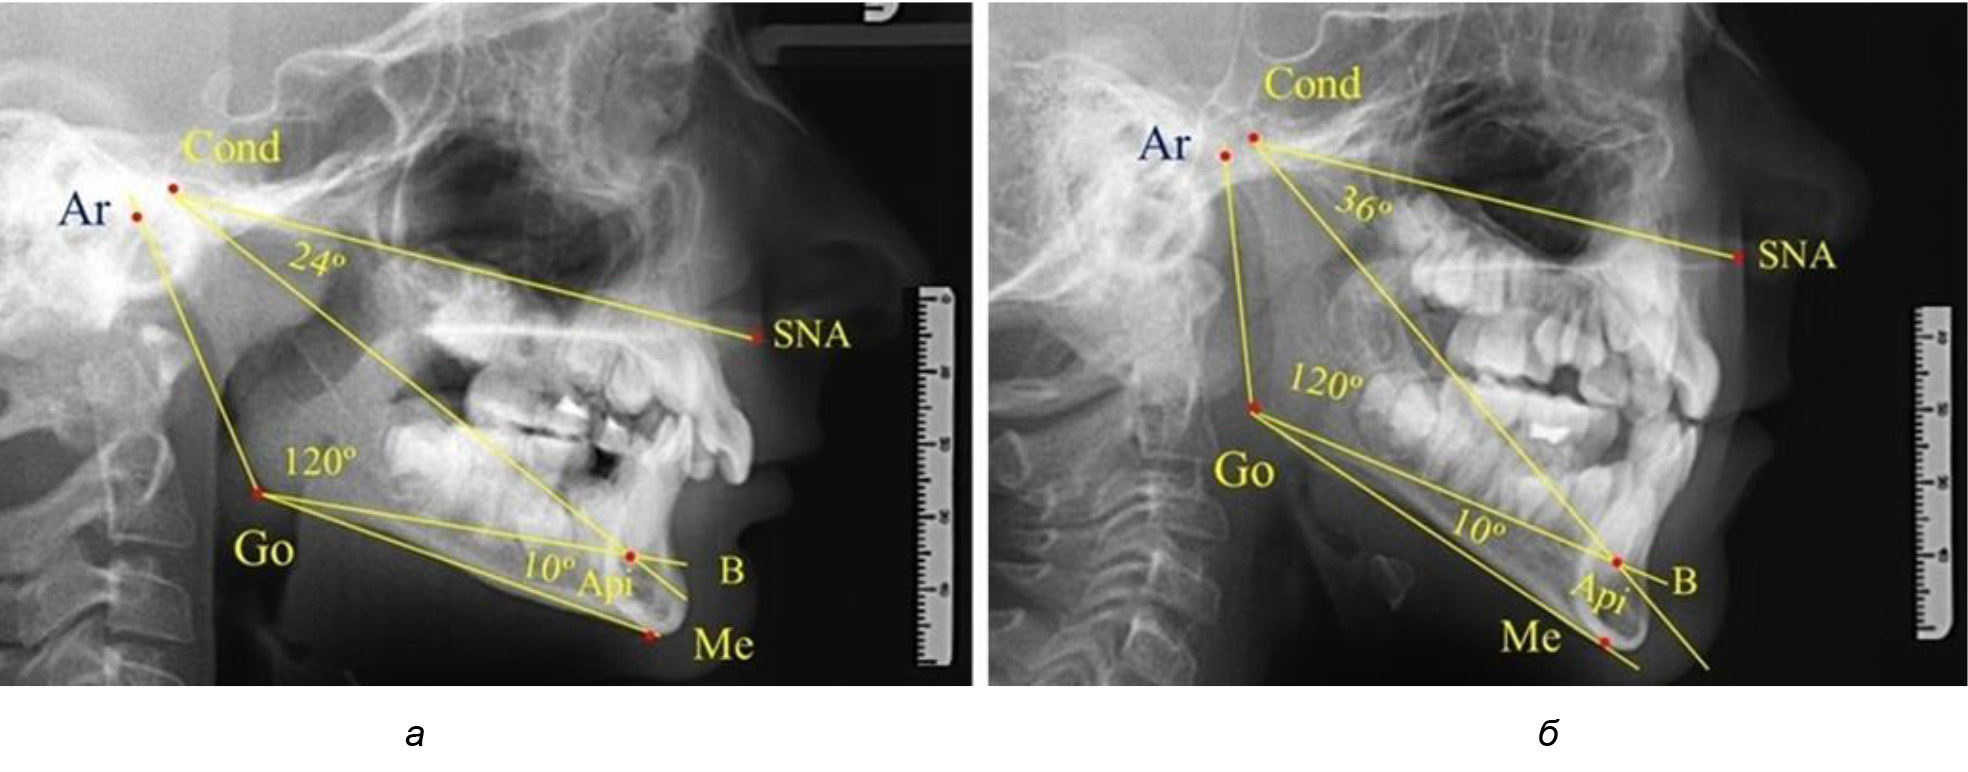

В результате исследования телерентгенограмм людей в периоде сформированного постоянного прикуса выявлено, что величина угла гнатической части лица SNA-Cond-Api в среднем по группе составил (29,96 ± 0,84)°. При анализе рентгенограмм с разными типами нижнечелюстного угла Ar-Go-Me достоверных различий величины угла гнатической части лица нами не отмечено и при физиологической окклюзии показатели варьировали от 27 до 33°, что определяло оптимальные параметры гнатического отдела лица.

В то же время нижнечелюстной угол варьировал в широких пределах, в частности от 112 до 127°, и его средние значения при физиологическом прикусе составляли (120,57 ± 1,43)°. При этом составляющие части нижнечелюстного угла имели различия. Так, показатель угла Ar-Go-Api варьировал от 110 до 117°, при средних значениях – (107,12 ± 1,73)°. Величина угла Api-Go-Me составляла в среднем (13,56 ± 1,09)° при минимальных значениях 6° и максимальном показатели 19°. Анализируя параметры нижнечелюстного угла на телерентгенограммах с различными типами нижнечелюстного угла, выявлено, что у людей с нейтральными типами угла (в пределах от 119 до 123°) средний показатель был (121,83 ± 0,62)°. Величина угла Ar-Go-Api составила (107,89 ± 1,62)°, а угол Api-Go-Me был (13,83 ± 1,12)°.

При вертикальном типе нижнечелюстного угла его средние значения составили (125,51 ± 0,44)°, и достоверно отличалась от показателей людей с нейтральными значениями нижнечелюстного угла. Величина угла Ar-Go-Api составила (115,49 ± 2,14)°, а угол Api-Go-Me был (13,97 ± 1,26)°.

Для горизонтального типа роста было характерно достоверное р ˂ 0,05 уменьшение нижнечелюстного угла до (115,57 ± 0,56)°. Величина угла Ar-Go-Api составила (102,71 ± 1,62)°, а угол Api-Go-Me был (12,86 ± 0,74)° (рис. 3).

Рис. 3. Особенности ТРГ при нейтральном (а), вертикальном (б) и горизонтальном (в) типе угла нижней челюсти в постоянном прикусе

Таким образом, вне зависимости от величины нижнечелюстного угла, показатели угла гнатической части лица были в пределах 30°, что может расцениваться в качестве оптимального физиологического показателя параметров гнатической части лица. Анализ ТРГ проведен у 31 ребенка в различные периоды дентального онтогненеза, включая прикус молочных зубов и различные группы прорезывания постоянных зубов.